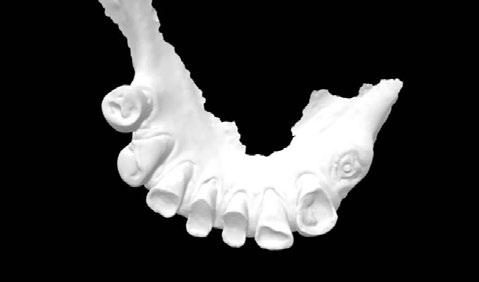

Exploración Intraoral

Presenta un estado oral deficitario. Parcialmente edéntula, con colapso de mordida, migración dental patológica, restauraciones de resina antiguas fisuradas y filtradas, transparencia y exposición de cámara pulpar secundaria a desgastes con pérdida de estructura e integridad de tejido dental importante (Figuras 1 a 4). Portadora a tiempo parcial de prótesis removibles desadaptadas de más de 10 años de antigüedad, refiriendo incapacidad de adaptación a este tipo de prótesis.

Figura 3. Visión intraoral oclusal mandibular. Figura 4. Visión intraoral frontal. Figura 1. Visión intraoral oclusal maxilar. Figura 2. Visión lateral izquierda intraoral. Figura 7. Escaneado intraoral maxilar con Dexis IS3700. Figura 8. Escaneado intraoral mandibular con Dexis IS3700. Figura 5. Visión extraoral lateral sonrisa.